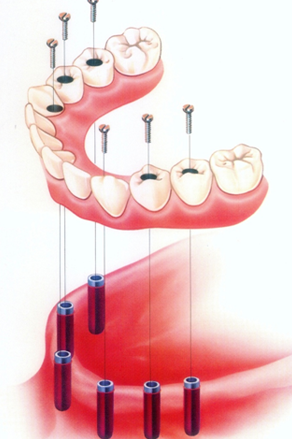

- Στην κάτω γνάθο τοποθετούνται 4-6 εμφυτεύματα

- Στην άνω γνάθο τοποθετούνται 6-8 εμφυτεύματα

Ο αριθμός αυτός των εμφυτευμάτων εξασφαλίζει την κατασκευή μιας σταθερής προσθετικής αποκατάστασης που θα αποκαθιστά την αισθητική και τη λειτουργία στη γνάθο. Σε μερικές μάλιστα περιπτώσεις είναι δυνατή η κατασκευή μιας προσωρινής αποκατάστασης την ίδια μέρα που τοποθετούνται τα εμφυτεύματα (άμεση φόρτιση εμφυτευμάτων). Η τελική προσθετική εργασία τοποθετείται 2-3 μήνες αργότερα σύμφωνα με τους κανόνες οστεωενσωμάτωσης.

Έξι οδοντικά εμφυτεύματα και ακίνητη κατασκευή